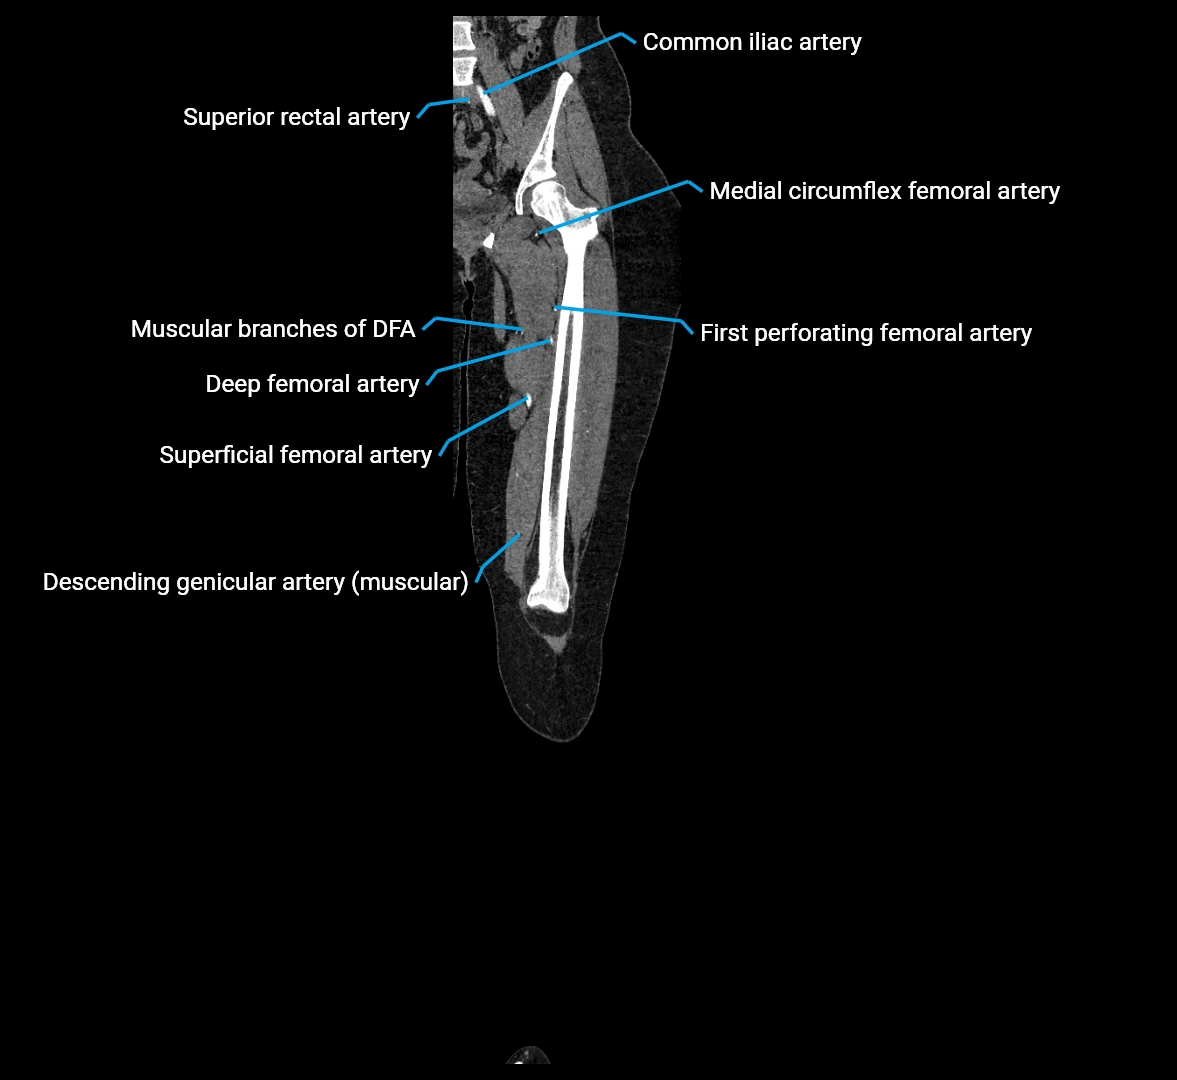

CT images

image